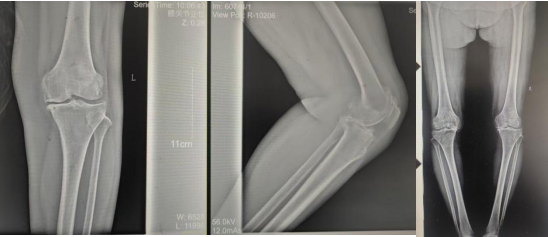

術(shù)前影像資料

因張女士患有高血壓病2級(jí)(高危)、心律失常(竇緩)且伴有肺部感染等并發(fā)癥。穆志亮主任和葉龍安主治醫(yī)師根據(jù)張女士的病情制定詳細(xì)手術(shù)方案,建議在全麻下行“左人工全膝關(guān)節(jié)置換術(shù)”。